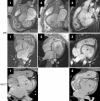

Results: Findings from the three patients were very similar: a truncated and spherical LV with abnormal diastolic and systolic function, invagination of fatty material into the myocardium of the defective LV apex, origin of a complex papillary network in the anteroapical LV, and an elongated right ventricle wrapping around the deficient apex.